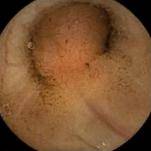

息肉可遍布除食管外的整个消化道,这些息肉的病理类型多为错构瘤性息肉(正常组织的异常排列),但具有独特的组织学特征:平滑肌细胞呈树枝状生长,形成特征性的“假浸润”表现。